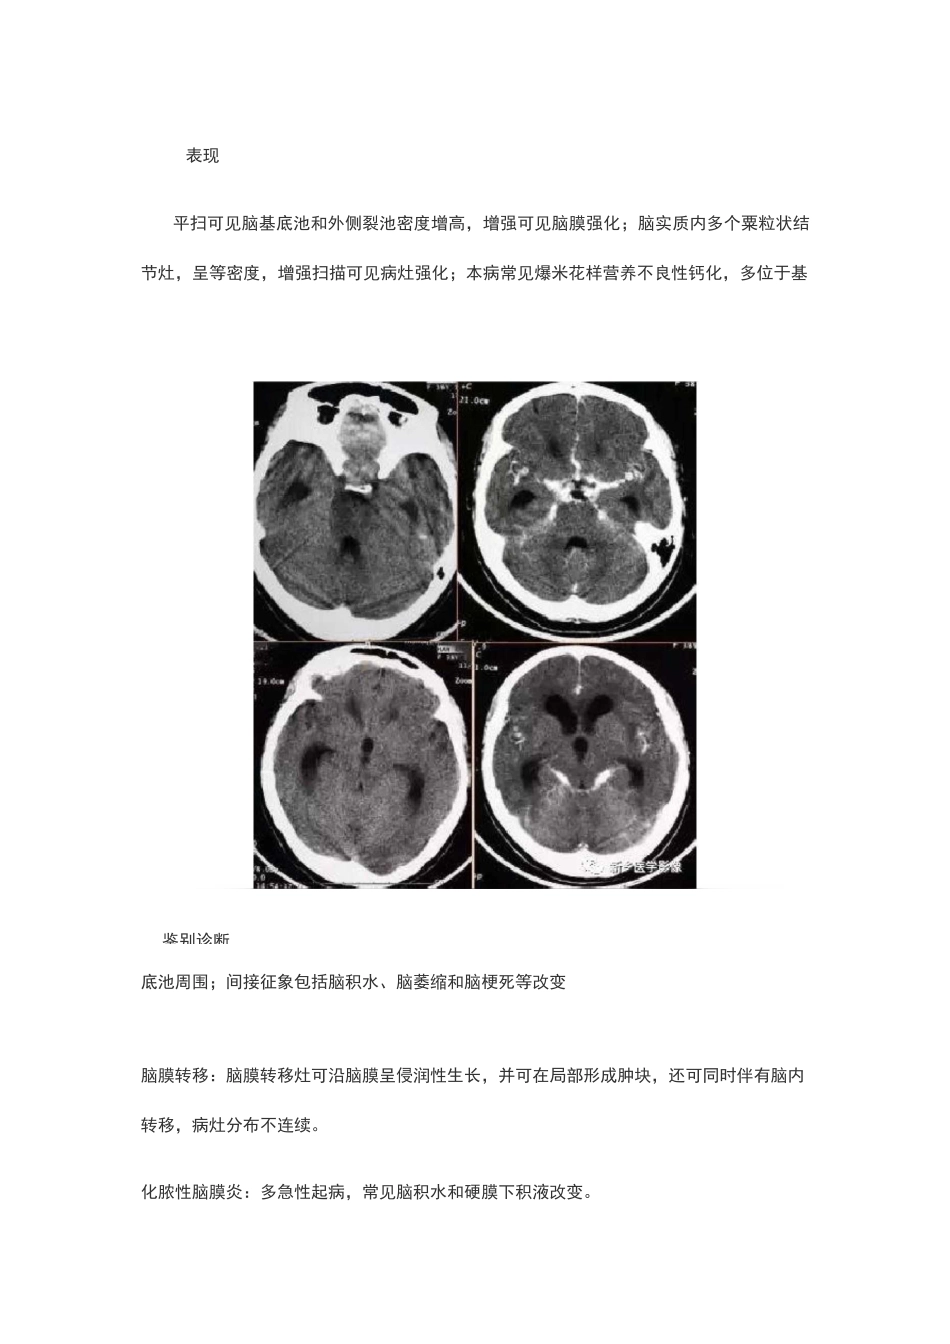

化脓性脑膜炎临床概述化脓性脑膜炎是常见的中枢神经系统化脓菌感染性疾病主要表现为发热、头痛、惊厥和颅内压增高等。表现平扫可见基底池和脑沟的正常形态消失,呈等密度改变,这是由于炎性渗出物填充脑池和脑沟所致;增强扫描可见脑膜强化;本病可并发脑积水,表现为脑室扩大;本病可并发硬膜下积液,表现为脑外新月形低密度区;本病并发脑静脉窦血栓时,增强扫描可见典型空三角征,此征象由强化的血流和血管壁与不增强的血栓共同组成;可并发出血性脑静脉梗死、脑炎或脑脓肿。鉴别诊断脑膜转移:脑膜转移灶可沿脑膜呈侵润性生长,并可在局部形成肿块,还可同时伴发脑内转移,病灶分布不连续。结核性脑膜炎:多数呈亚急性起病,常有纟吉核接触史,分布以基底池为明显,并可见多发粟粒状^吉节灶。化脓性脑膜炎患者行脑脊液检查时可见脑脊液外观浑浊,白细胞增多,以中性粒细胞为主,细胞涂片或培养可找到病原菌。结核性脑膜炎临床概述结核性脑膜炎是颅内结核的最主要表现形式,主要表现为发热、头痛、颅内压增高、局灶性神经功能障碍等症状和体征,病理主要为脑膜增厚和肉芽组织增生。,鉴别诊断表现平扫可见脑基底池和外侧裂池密度增高,增强可见脑膜强化;脑实质内多个粟粒状结节灶,呈等密度,增强扫描可见病灶强化;本病常见爆米花样营养不良性钙化,多位于基底池周围;间接征象包括脑积水、脑萎缩和脑梗死等改变脑膜转移:脑膜转移灶可沿脑膜呈侵润性生长,并可在局部形成肿块,还可同时伴有脑内转移,病灶分布不连续。化脓性脑膜炎:多急性起病,常见脑积水和硬膜下积液改变。结核性脑膜炎患者行脑脊液检查示细胞数多小于个,以淋巴细胞为主,糖含量减少,蛋白含量升高,涂片抗酸染色可找到结核分枝杆菌。病毒性脑炎临床概述本病临床表现为头痛、发热、智力减退、癫痫等症状,严重者可昏迷甚至死亡。表现病毒性脑炎早期(在发病天),表现可正常,随病情进展,多表现为颞叶境界不清的低密度病变;增强可见境界不清的斑片状或脑回状强化;病变严重者可见脑实质内不规则高密度出血灶;本病后遗症改变包括脑软化、脑萎缩和营养不良性钙化等鉴别诊断脑梗死:发生脑梗死时,其异常血管分布区与病变血管的血供区一致,增强扫描梗死区域可见轻度脑回样强化。脑肿瘤:病灶占位效应明显,增强后多呈环状或实性强化。脑脓肿临床概述急性感染症状:头痛、发热、寒战、乏力、嗜睡等;颅内压增高症状:头痛、呕吐视盘水肿;伴有不同程度的精神和意识障碍,并局限性癫痫发作;脑疝:可发生小脑幕切迹疝及枕骨大孔疝;可并发急性化脓性脑室炎或脑膜炎。表现平扫显示不规则的低密度区,边界欠清;增强扫描显示脓肿壁呈厚壁环形强化,边缘光整,中央不强化,病灶周围可见明显脑水肿。鉴别诊断慢性脑内血肿:病变可环形强化,壁可厚可薄,呈低密度或等密度,有近期急性脑出血病史。胶质母细胞瘤:可呈环形强化,壁形态不规则,可见壁结节。脑转移瘤多有原发肿瘤病史,脑内病变常多发,小病灶即可见明显的脑水肿。在脑脓肿鉴别诊断方面,应用有助于脑脓肿和脑内环形强化肿瘤鉴别,脑脓肿脓液中含大量蛋白,脓液黏稠,水分子的弥散受限,高信号,降低。肿瘤坏死及囊性肿瘤内水分增多,弥散增加,低信号,值升高。病因包括耳源性、血源性及其彳也等。直接蔓延的病灶多为单发,幕上颞叶多见,血行感染的病灶好发于皮质和皮髓质交界区,常多发;病理可分为脑炎期、化脓期和脓肿壁形成期,吧、脓肿壁内层为肉芽组织和巨噬细胞,中层为胶原纤维,外层为胶质增生。脑结核瘤临床概述脑结核瘤为结核分枝杆菌在脑部引起的慢性肉芽肿;本病起病隐袭,可表现为结核中毒症状,如低热、乏力盗汗等;本病一般以癫痫发作、精神障碍、颅内压增高为主要表现;可发生于田可年龄,成人幕上多见,可出现头痛、癫痫、偏瘫、失语等;儿童幕下多见,可出现颅内压增高和小脑共济失调等。表现成熟前期:平扫显示呈低密度区,无强化。成熟期:表现为圆形或类圆形等密度或稍高密度病灶,边界不清,周围有水肿,增强后病灶呈结节样强化。干酪样坏死期:平扫呈稍高密度或等密度区,少数可有钙化,增强后呈环形强化,表现典型者环形病灶...